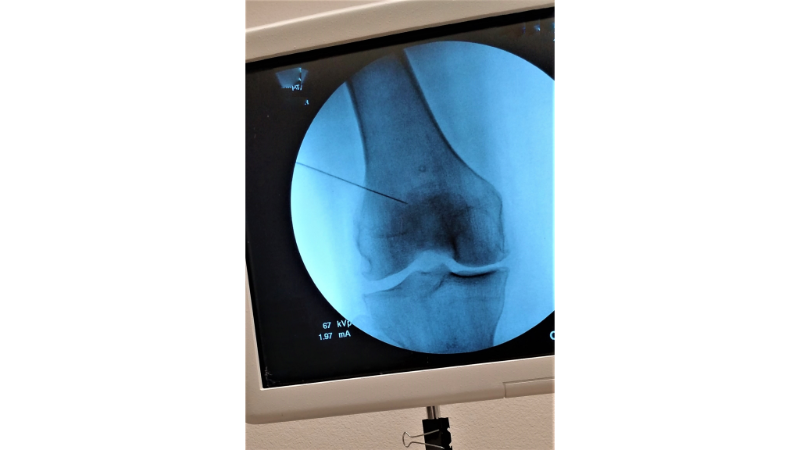

A dislocated kneecap, medically referred to as patellar dislocation, occurs when the patella bone shifts outward from the groove called the femoral trochlea. Normally, the patella moves up and down within this groove located at the front of the thigh bone. However, when stability is lost, the bone slips out and moves beyond the joint.

About Patella Dislocation

A patellar dislocation occurs when the kneecap shifts outward from its normal position. As a result, it loses alignment with the knee joint. This condition can develop after sudden trauma or due to long term structural problems. Therefore, patellar dislocation may appear as either an acute or a chronic issue.

Acute patellar dislocation usually happens after a sudden movement, twisting, or a direct impact to the knee. These dislocations often occur for the first time. They present with severe pain, swelling, and limited movement. Right after the trauma, the patient often struggles to move the knee. Early intervention is crucial in these cases.